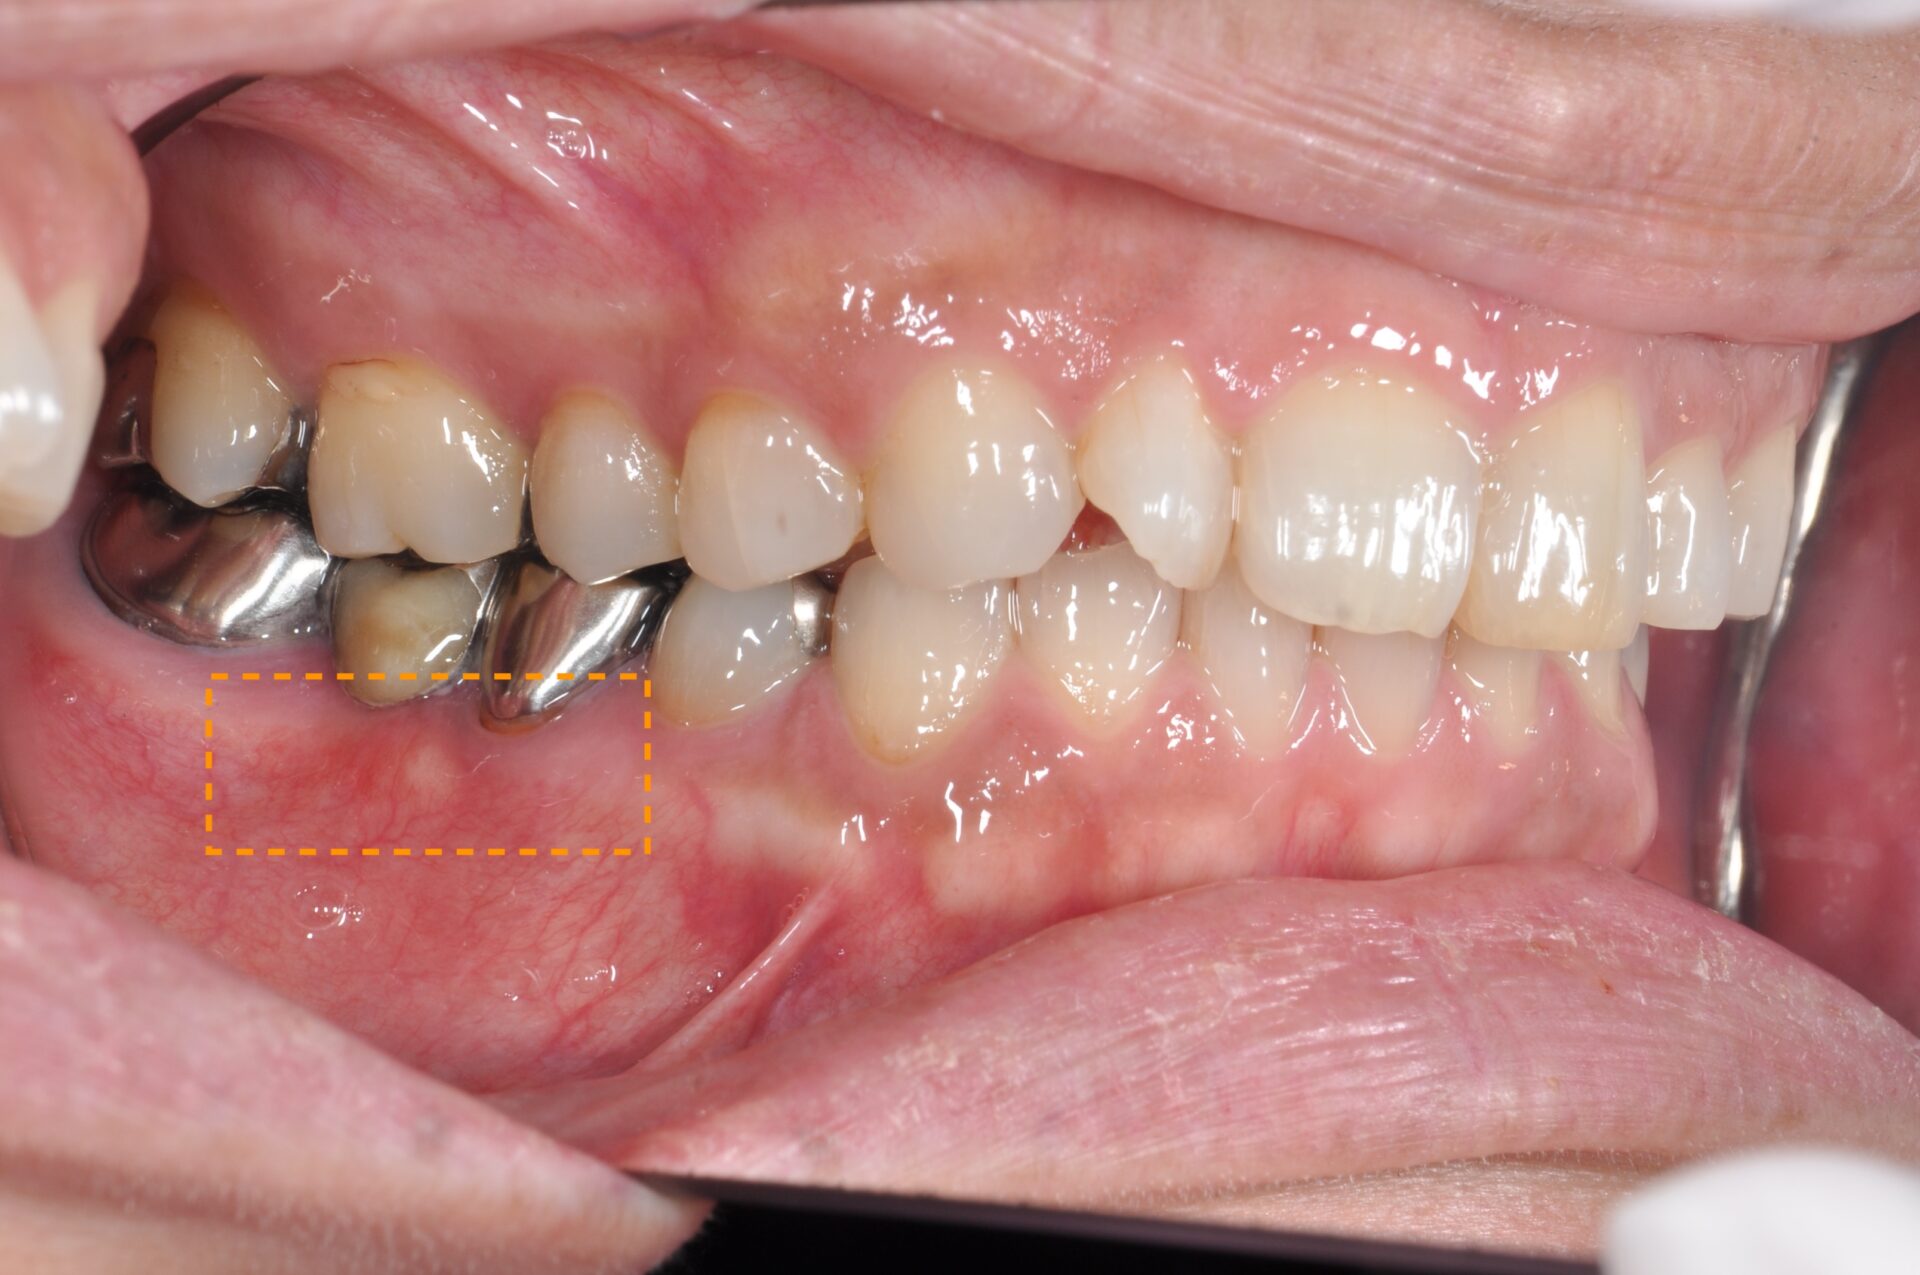

FGG(遊離歯肉移植術) 臨床例①

患者さんは、左下奥歯の周囲に付着歯肉が不足しており、ブラッシングの際に痛みがあり清掃が難しく、炎症を繰り返していました。歯肉が薄く柔らかいため、長期的な安定には不安があり、遊離歯肉移植術(FGG) を行うこととしました。

術前